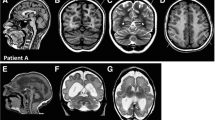

Clinical reports of 3 novel cases

For the purpose of this study the clinical course of three individuals, who presented between 1999 and 2016 at our Center of Developmental Neurology and Social Pediatrics for investigation of the etiology of developmental delay, was retrospectively summarized after pathogenic missense variants in TUBA1A had been identified. In summary, we present novel clinical data for two boys aged 13 years 7 months (individual i084n) and 11 years 6 months (individual i085n) and a 9 years 3 months old girl (individual i086n) with global developmental delay and neuroradiological abnormalities due to TUBA1A-associated tubulinopathy. The identification of the TUBA1A variant in the girl was part of a previous publication without detailed clinical description (reported as ID S_006) [16]. Narrative case reports with representative MRI planes for all three individuals and facial phenotype pictures for i086n (Additional file 1: Figure S1-S3) are provided in the Supplementary notes.

Additional file 1:

Figure S1. Cranial MRI planes of individual i084n. Figure S2. Cranial MRI planes of individual i085n. Figure S3. Cranial MRI planes and clinical pictures of individual i086n. Figure S4. Additional computational scores for TUBA1A variants. Figure S5. Analysis of the variant cluster around amino acid position 400. Figure S6. Comparison of computational scores for TUBA1A variants identified in fetuses and born individuals. Figure S7. Matrix plot of all HPO phenotype categories. Figure S8. Association plots for recurrently affected amino-acid positions and all neuroradiological features. Figure S9. Association plots publications describing ≥ 5 individuals and all neuroradiological features. Table S1. Barthel Index of Activities of Daily Living [3] of the 3 individuals with TUBA1A variants. (DOCX 2946 kb)